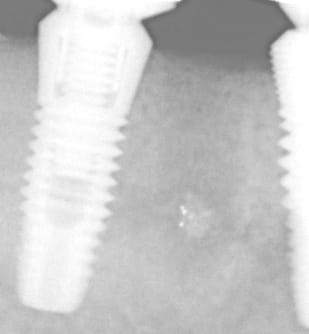

la rvg en question

Image o 3 av8pra - Eugenol

A mon avis cette reconstruction osseuse est à mettre en rapport avec plusieurs éléments :

1) technique en un temps si il avait fallu faire un lambeau jamais cela ne se serait produit

2)pas de curetage

3)mise en fonction malgrè tout donc stimulation osseuse

4)maintenance douce par le patient (qui nous a quand même oublié trois ans...)

5)j'ai changé de capteur radio entre temps avec une définition sans comparaison et je pense que malgré tout avec un capteur précis les premières rvg de 2001-2002 auraient montré un semblant de trame osseuse .quant aux doutes sur la chronologie regardez la marque des capteurs et vous verrez que l'on n'utilise pas une rolls dans un premier temps puis un solex après...